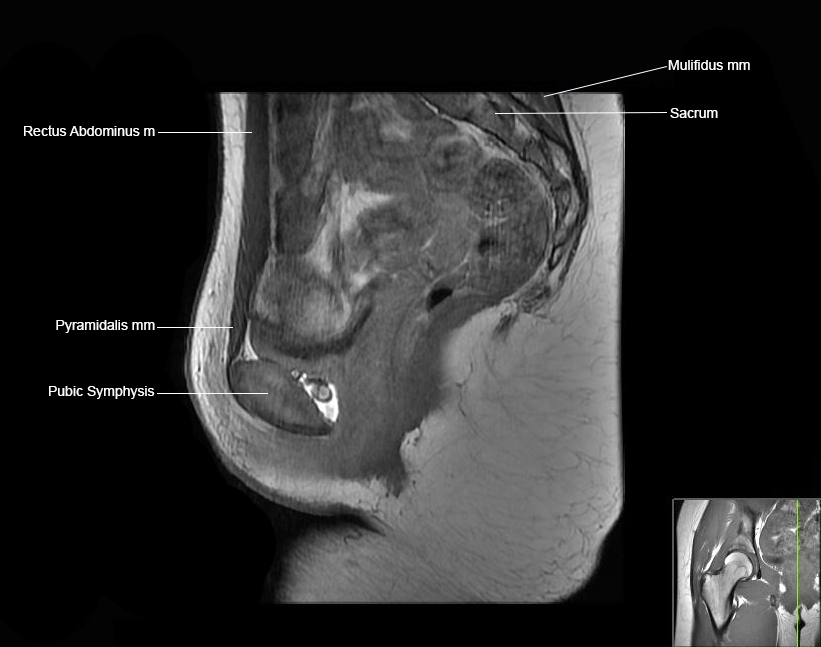

Hip

Basic Hip MRI

MRI Hip Anatomy

Scroll using the mouse wheel or the arrows